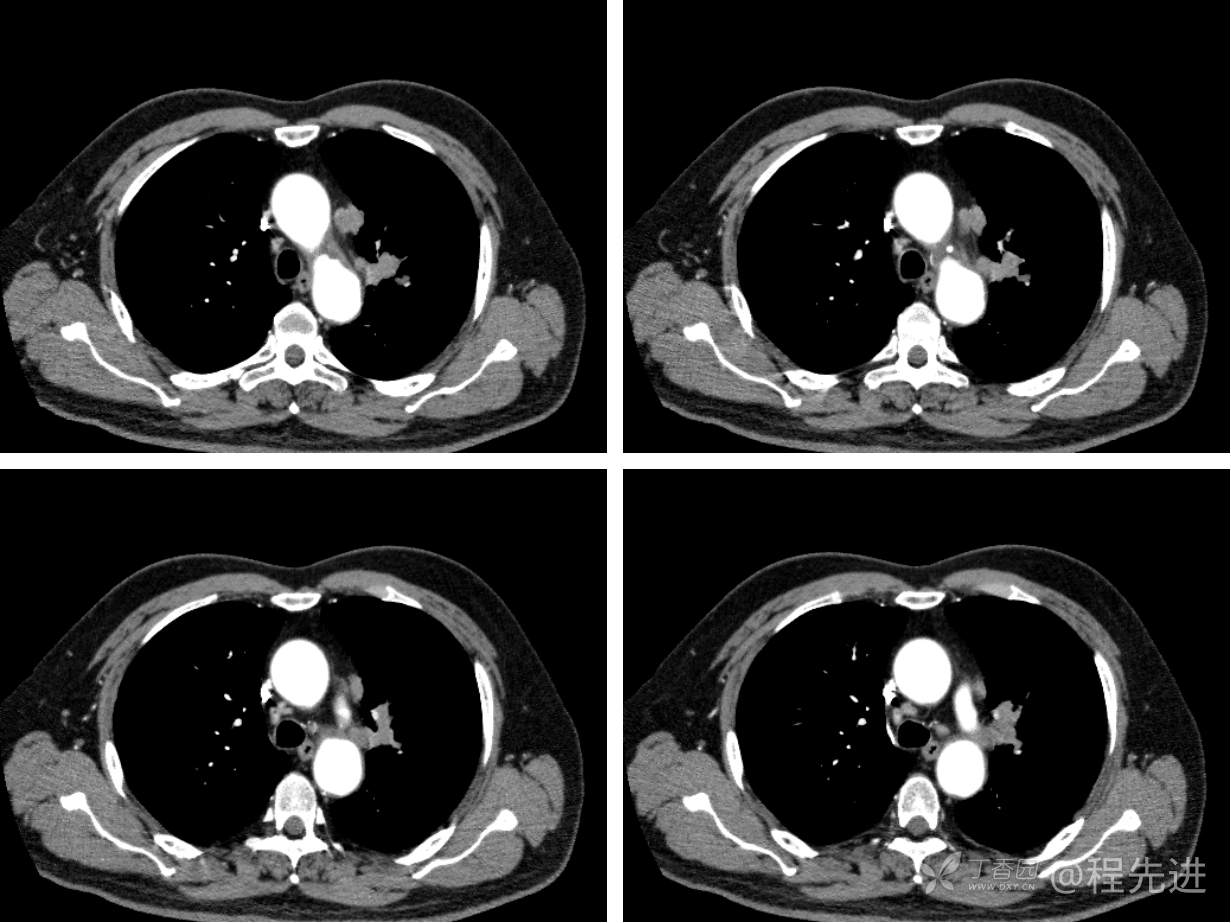

现病史概要:患者入院前约半月无明显诱因下出现咳嗽、胸闷症状,无明显发热症状,咳少量白痰,无明显咯血、喘息、头晕等不适,就诊我院查胸部CT示上纵膈肿物,左肺上叶支气管内肿物,现为行进一步治疗收入胸外科,患者近来饮食睡眠尚可,二便如常。